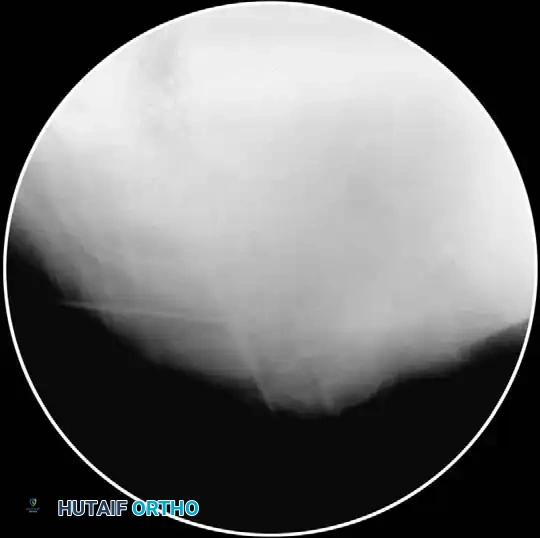

- Aspiration and Contrast: Aspirate to ensure no CSF or blood return. Attach a 5-mL syringe containing 1.5 mL of nonionic contrast dye (e.g., Iohexol).

- Epidurogram Confirmation: Inject the contrast under live fluoroscopy to produce an epidurogram. Adjust the C-arm to a lateral perspective to definitively document posterior epidural spread and rule out intrathecal or intravascular flow.

- Contrast Flow: Remove the stylet. Aspirate vigorously. Inject 0.5 mL of nonionic contrast under live fluoroscopy. You must observe filling of the oval neuroforamen and distal flow along the exiting nerve root. If rapid vascular washout is seen, abort the procedure immediately.

- Contrast Injection: Live fluoroscopy during contrast injection must demonstrate medial flow into the epidural space and lateral flow outlining the exiting spinal nerve.